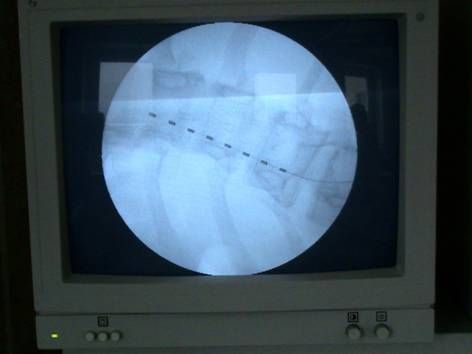

Тестовый электрод имплантируется в эпидуральное пространство чрескожно с помощью иглы Туохи под рентгеноскопическим контролем. Наружная контактная группа электрода присоединяется к портативному наружному нейростимулятору при помощи гибкого кабеля. Длительность тестового периода неоднозначна: с одной стороны более длительный период теста позволяет получить более подробную картину программирования, а с другой повышает риск инфекционных хирургических осложнений. Публикации различных авторов несут самые разнообразные сроки, однако по рекомендации компании изготовителя средний срок тестовой стимуляции не должен превышать 14 дней. За этот период пациент отвечает на вопросы наиболее комфортного режима парестезии, уменьшения болевого синдрома, изменения качества жизни и т.д.

Контроль за проведением тестового электрода

Флюороскопический контроль во время операции является необходимым условием для контроля положения иглы, уровня и места установки дистального конца электрода. Электроды чаще всего устанавливаются ростральнее неврологического уровня боли на стороне симптоматики.

После тщательной обработки операционного поля выполняется небольшой разрез в проекции остистых отростков, на фоне тщательного гемостаза отсепаровыватся паравертебрально поясничная фасция на уровне пункции эпидурального пространства (зависит от уровня неврологического проявления боли). Под углом 45• сагиттально и по направлению к средней линии под местной анестезией иглой Туохи выполняется пункция эпидурального пространства под контролем ЭОП. Также, для контроля попадания в эпидуральное пространство используется шприц низкого давления. При нахожении кончика иглы в эпидуральном пространстве исчезает ощущение резистентости в шприце, жидкость (как правило стерильная вода для иньекций) свободно проходит. Затем по игле вводится проводник для дополнительного контроля свободного проведения электрода. Далее под контролем ЭОП на нужный уровень проводятся электроды. Вид и размер элекродов подбирается в зависимости от задач, решаемых хирургом. Электрод проводится на микропроводниках, входящих в набор и облегчающих установку. Форсированное проведение электрода не рекомендуется. После установки электрода наружная контактная группа присоединяестся кабелем к программатору врача или тестовому стимулятору для подтверждения результатов тестовой стимуляции. При получении положительного результата приступают к монтажу всей системы.